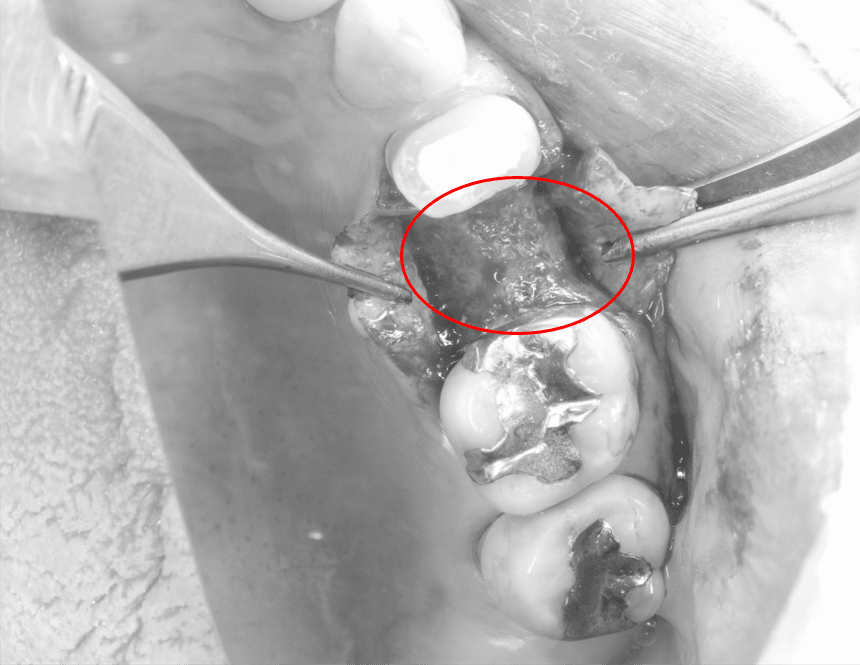

インプラントの2次オペ

こんんにちは。南館歯科クリニックの院長の木村です。 左下臼歯部のインプラントの症例です。 入れ歯を使用していましたが、どうしても抵抗があるということで、相談の結果、インプラントで治療を行…